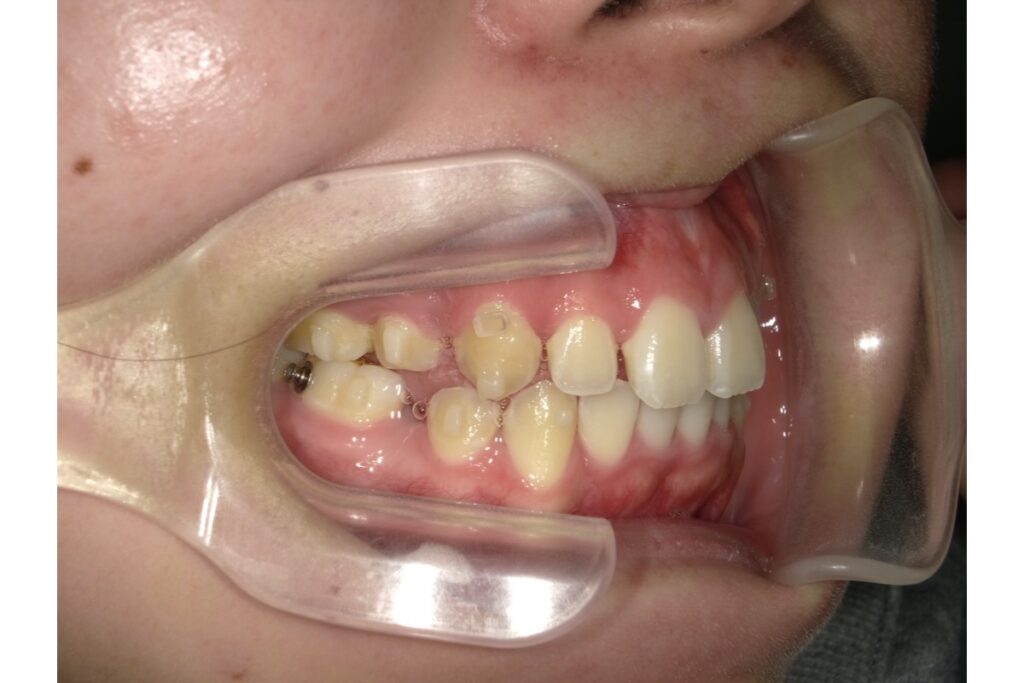

下記写真は初診時のものになります ↓

前歯を引っ込めたいという主訴だったので、抜歯をしての治療をすることになりました。インビザラインでは、歯を抜いての治療にも対応しております。歯を抜いた後、その隙間を使用して前歯を中に入れていきます!

抜歯をした場合は、アタッチメントの力だけでは歯を動かしていくには足りないので、顎間ゴムが必須になってきます。